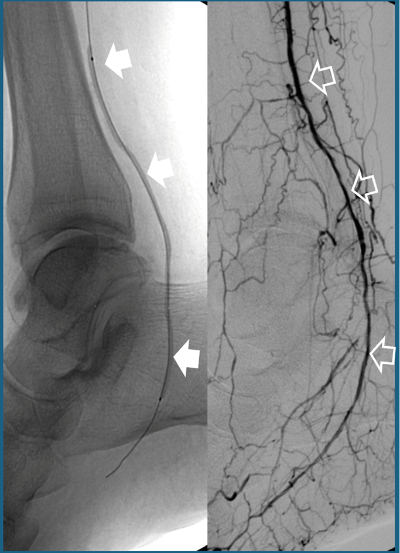

- Angioplàstia amb o sense stent: mitjançant un catèter es dilata l’artèria bloquejada (Fig. 1). Si això no és suficient per mantenir el vas obert, s’hi col·loca un petit dispositiu metàl·lic (stent) que el manté obert.

Fig.1. A: Angioplàstia amb catèter baló (fletxes blanques sòlides) d’un vas distal de la cama oclòs. B: resultat final amb el vas reobert (fletxes blanques buides).